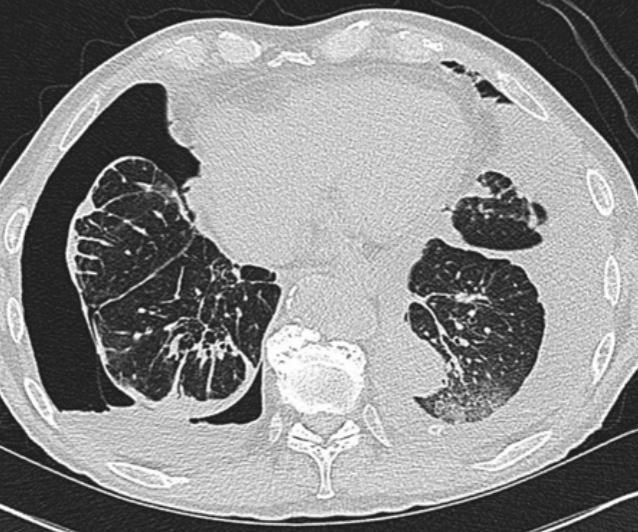

14/Imaging of trapped lung will typically show pleural thickening and loculation. An air contrasted CT can be used to better visualize the visceral pleura rind or you can use direct visualization with video-assisted thoracoscopy. @ReenaHem @ERitterMD @VCURadRes @MarkZieglerMD

16/ Management of an asymptomatic trapped lung is NOT pleural drainage as the effusion will just re-accumulate. However, decortication of the visceral pleura rind with VATS is typically your treatment for symptomatic patients who are surgical candidates. @VCUIMClerkship